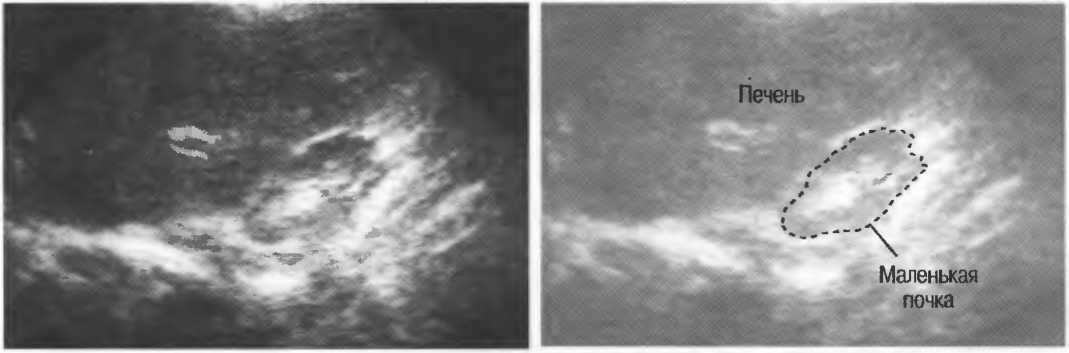

Затухание

Ткани тела поглощают и рассеивают ультразвук по-разному. Высокие частоты поглощаются и рассеиваются (гасятся) в большей степени, чем низкие. Поэтому, чтобы достичь более глубоких тканей, необходимо использовать более низкие частоты, так как менее вероятно, что эти волны затеряются при прохонодении через ткани. На практике оптимально использовать частоту около 3,5 МГц для глубокого сканирования у взрослых и частоту 5 МГц и выше для исследования более худых пациентов или детей. Частота 5 МГц и выше используется для исследования поверхностных органов у взрослых.

Выбор соответствующего датчика

Наилучшим датчиком для общей практики является конвексный датчик с частотой 3,5 МГц с фокусировкой на расстоянии 7-9 см. Если такого датчика нет, необходимо наличие линейного секторного датчика с частотой 3,5 МГц. При необходимости исследования детей и худых взрослых желательно дополнить набор датчиком с частотой 5 МГц с фокусировкой 5-7 см.

1. Ультразвуковые исследования в акушерстве. Для общих исследований в акушерстве используется линейный или конвексный датчик с частотой 3,5 или 5 МГц с глубиной фокусировки на 7-9 см. Если закупается только один датчик, выбирайте датчик с частотой 3,5 МГц. Датчик с частотой 5 МГц предпочтителен на ранних сроках беременности. В поздние сроки беременности лучше использовать датчик с частотой 3,5 МГц.

2. Ультразвуковые исследования в общей практике. Если проводятся исследования в верхней части живота и таза у взрослых, в том числе и акушерские исследования, предпочтительнее выбор секторного или конвексного датчиков с частотой 3,5 МГц с глубиной фокусировки на 7-9 см.

3. Ультразвуковые исследования в педиатрии. Для детей необходим датчик с частотой 5 МГц с глубиной фокусировки на 5-7 см. При исследовании мозга новорожденного используется секторный датчик с частотой 7,5 МГц с глубиной фокусировки на 4-5 см (этот датчик также используется для исследования яичек и структур шеи у взрослых).